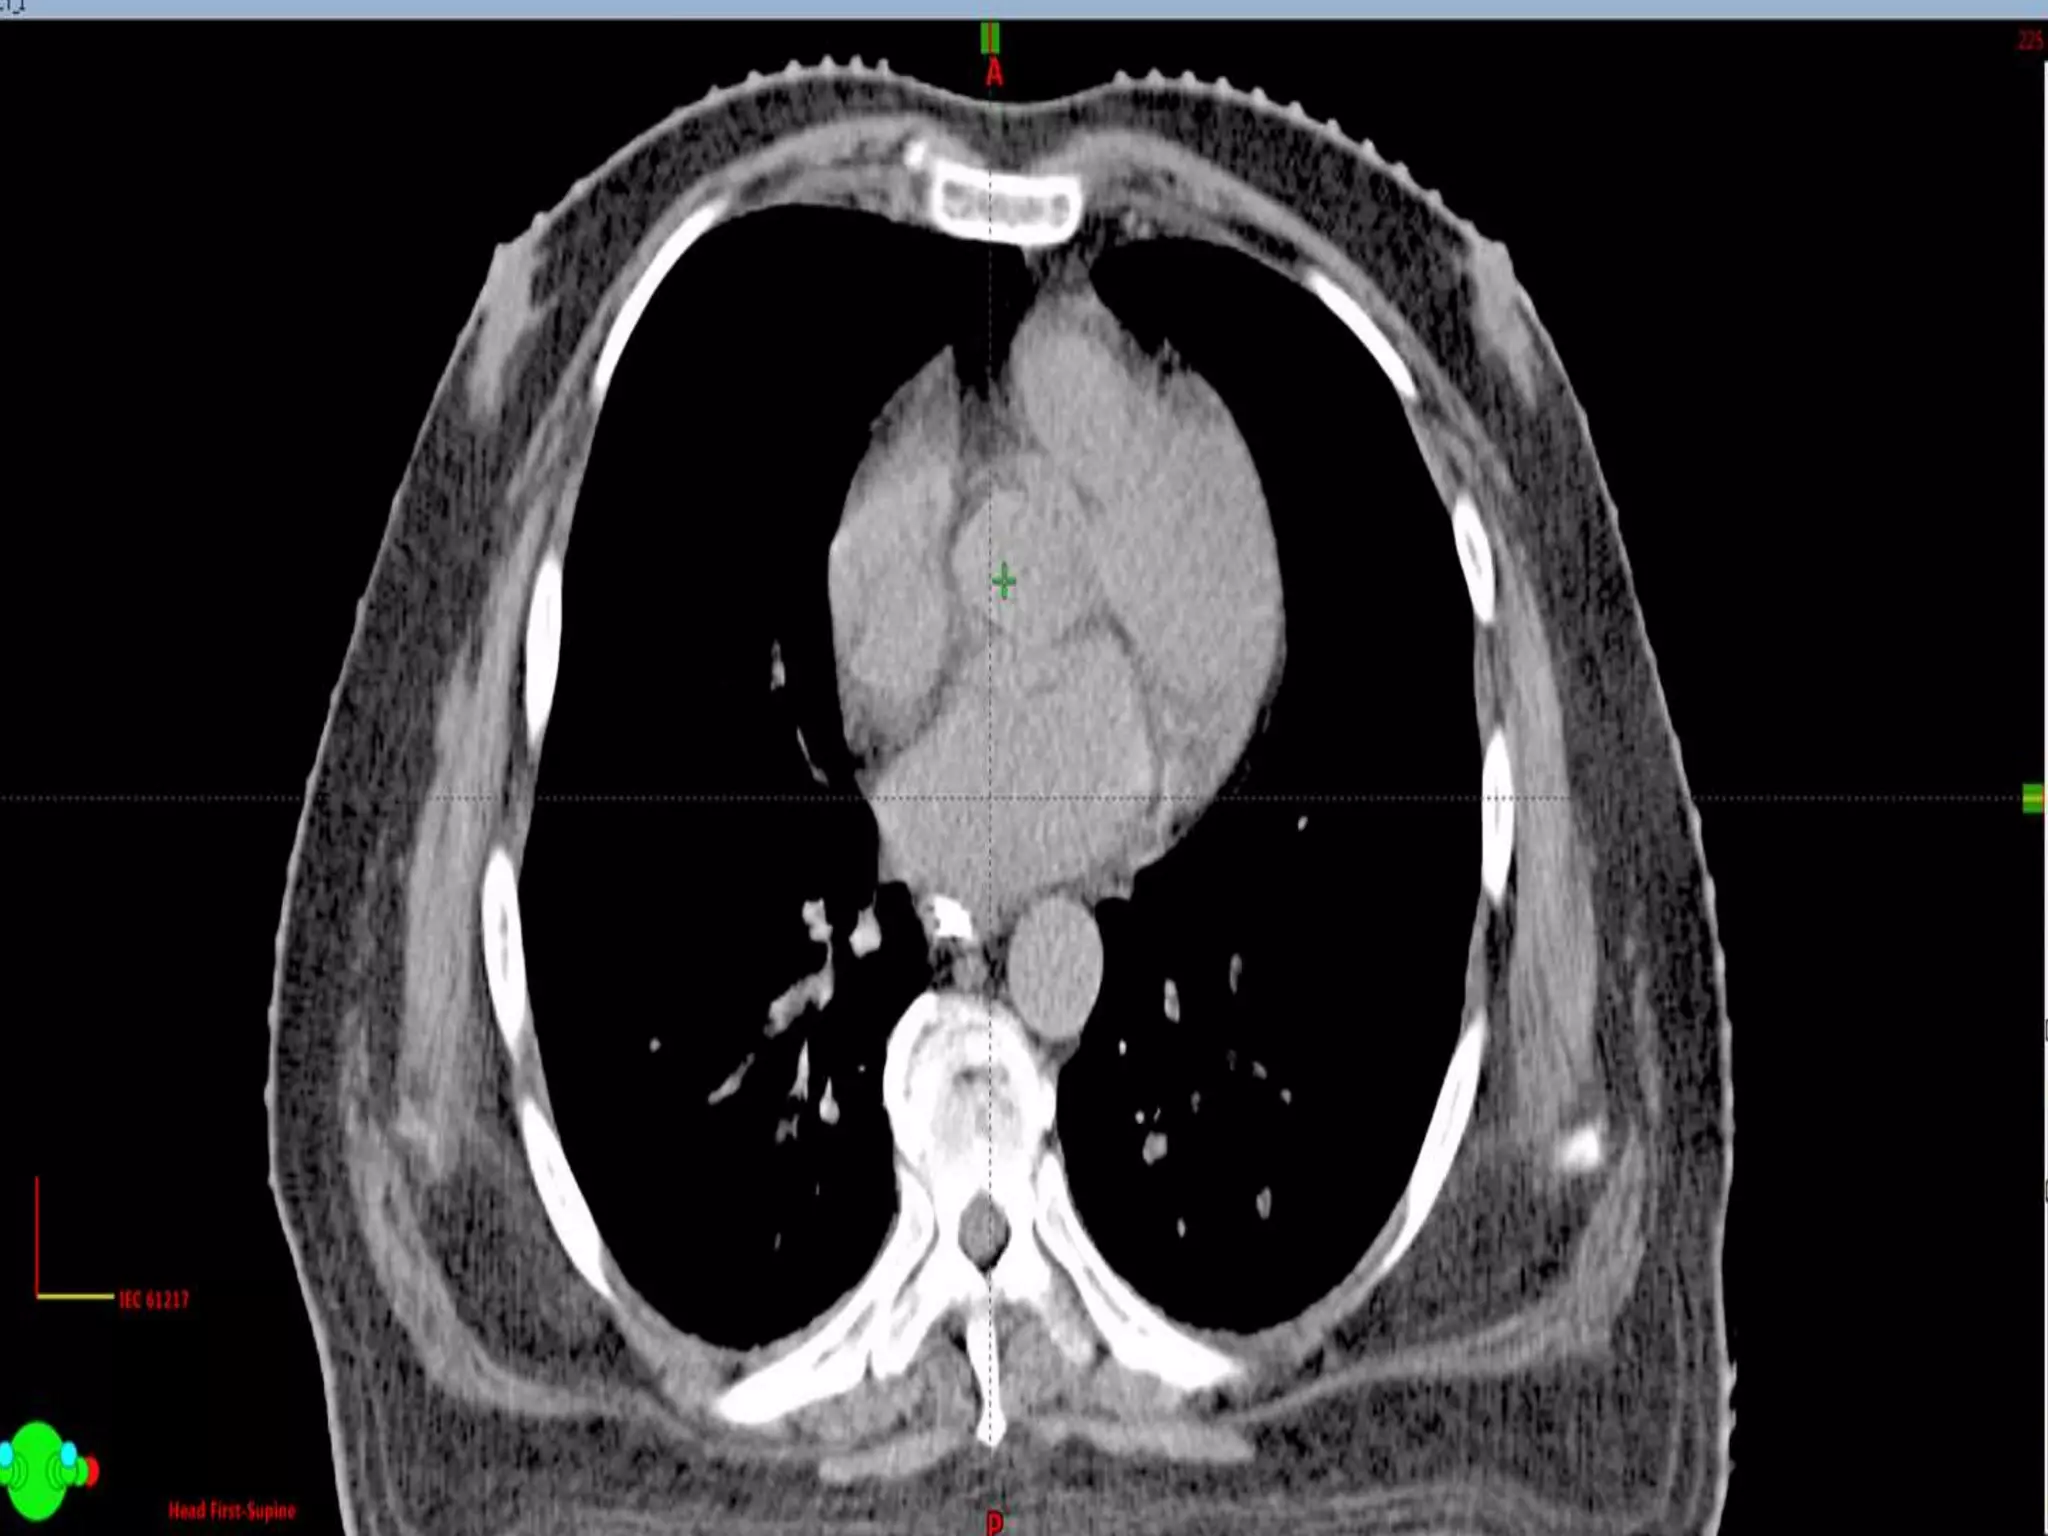

Graphically it means

-500 to 200

-200 to 100

25 to 40

25

HU value equates the Electron Density of the Tissue

Graphically it means -500to 200 -200 to 100 25 to 40 25

HU value equatesthe Electron Density of the Tissue